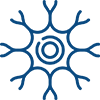

Stage 1: The Mucus Trap

Everyday exposure to harmful airborne toxins triggers your lungs to overproduce sticky mucus as a defense mechanism.

But instead of protecting you, the mucus traps more toxins—blocking your airways and triggering endless coughing.

Stage 2: The Airway Squeeze

Over time, this mucus hardens into thick, sticky layers that narrow your airways.

Result? Oxygen deprivation that leaves you breathless, fatigued, and weak—turning simple activities into exhausting struggles.